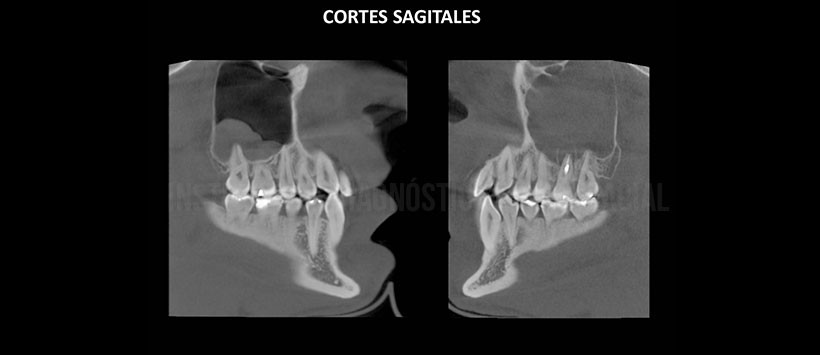

A la evaluación de la tomografía volumétrica en cortes axiales (Figura 2), coronales (Figura 3), sagitales (Figura 4), transaxiales (Figura 5) y tangenciales (Figura 6) se aprecia a la pieza 26 con restauración coronaria, espigo en raíz palatina y obturación de conductos radiculares, con restos de material a nivel periapical de raíz disto-vestibular. Se visualiza proceso osteolítico peri-radicular en las tres raíces que se extiende de la zona de furca hasta el piso del seno maxilar el cual se observa desplazado cefálicamente, adelgazado y con zonas de erosión en relación a contenido isodenso en la totalidad del seno maxilar izquierdo que ocasiona la obstrucción de ostium.